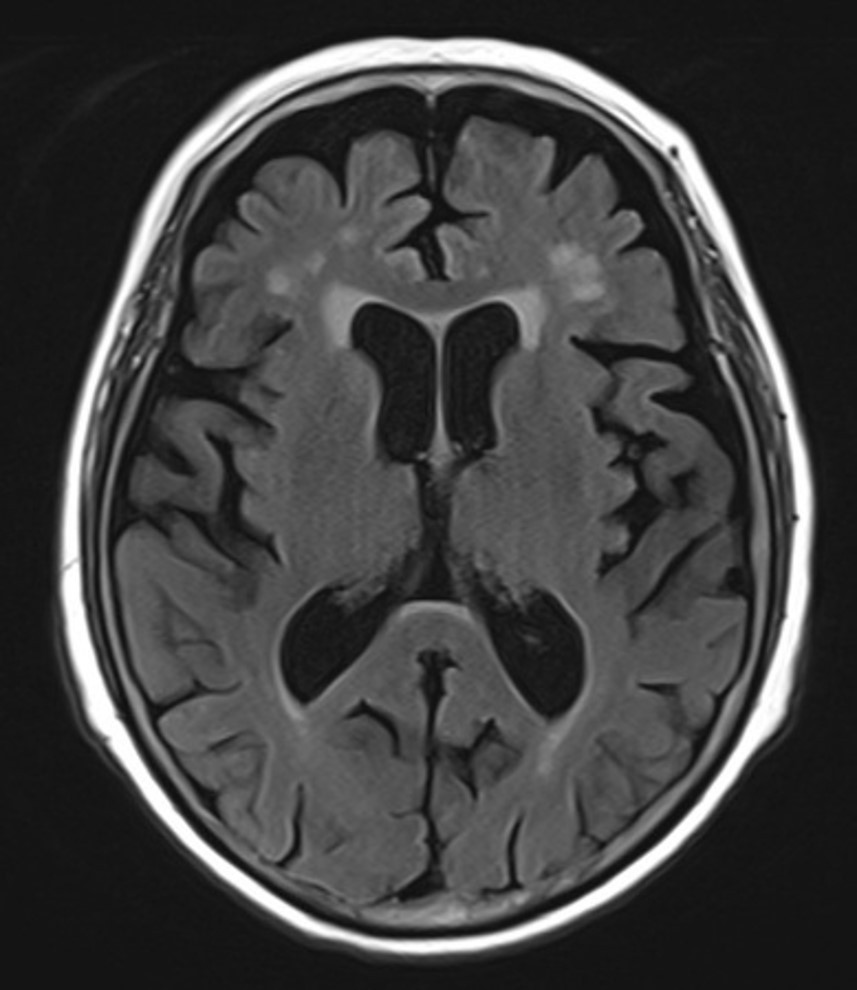

뇌 MRI, MRA를 통한 뇌혈관 상태 평가부터 시작했어요.

다행히 급성 뇌경색 같은

심각한 병변은 발견되지 않았어요.

하지만...

연령에 비해서는 좀 진행된 뇌위축 소견이 보였고,

인지기능 평가에서도

유의한 점수 저하가 관찰됐어요.

그림11.jpg 촬영 일시: 2025.07.11

<Fig 1. 뇌 mri>

결론적으로는 초기 치매를 진단할 수 있었습니다.